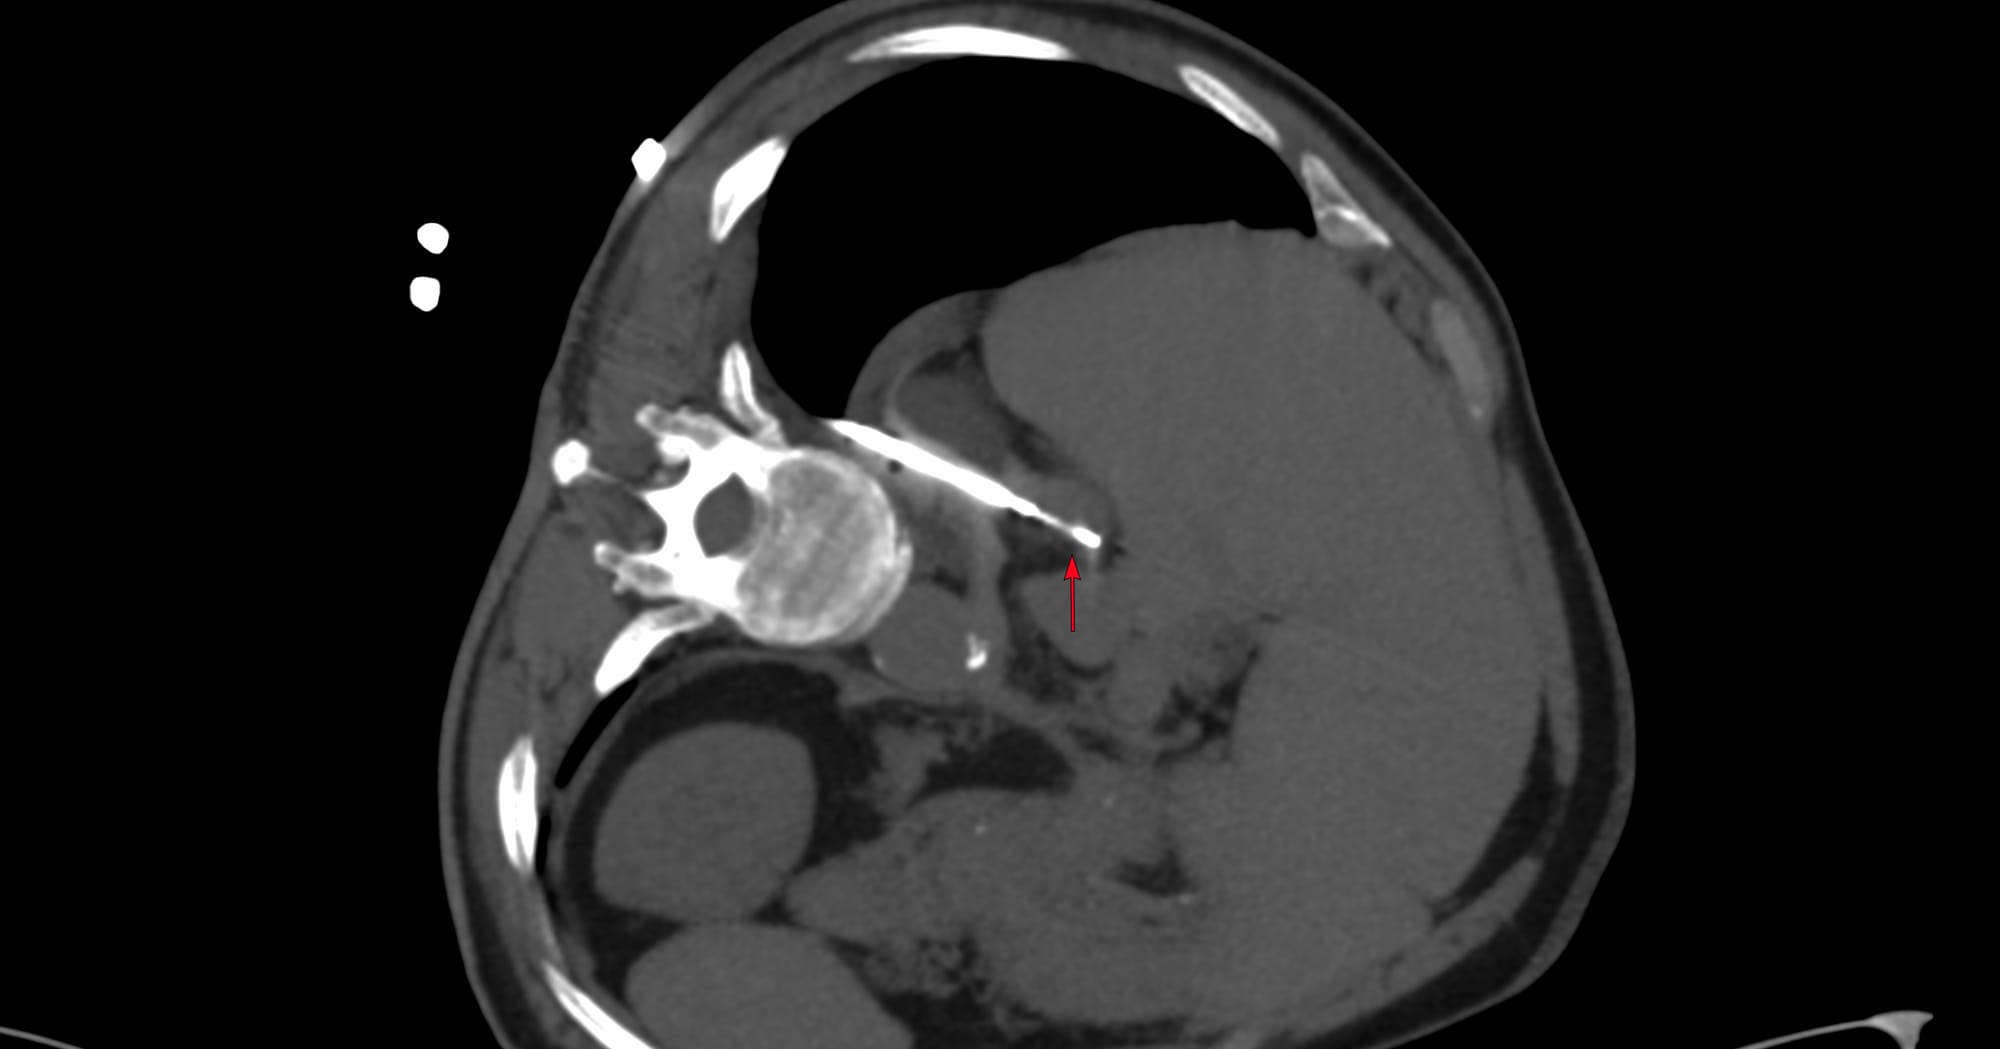

Case 171 - Splenic Mass Biopsy

Bhavin Jankharia - 04 December 2025